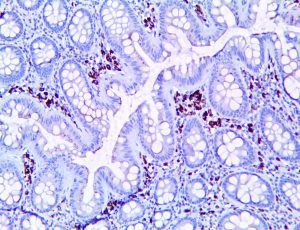

This activation induces inflammatory monocytes to highly express IL-6, starting a localized and then systemic cascade effect that results in hyperproduction of IL-6, which accelerates the inflammatory process. Because IL-6 also increases vascular permeability, excessive levels cause blood vessels to become very leaky. This, along with clotting factors released from vascular endothelial cells, stimulates the coagulation cascade, resulting in microthrombosis (tiny clots), which leads to ischemia and tissue death of the kidney, intestines, heart, liver, brain and extremities.